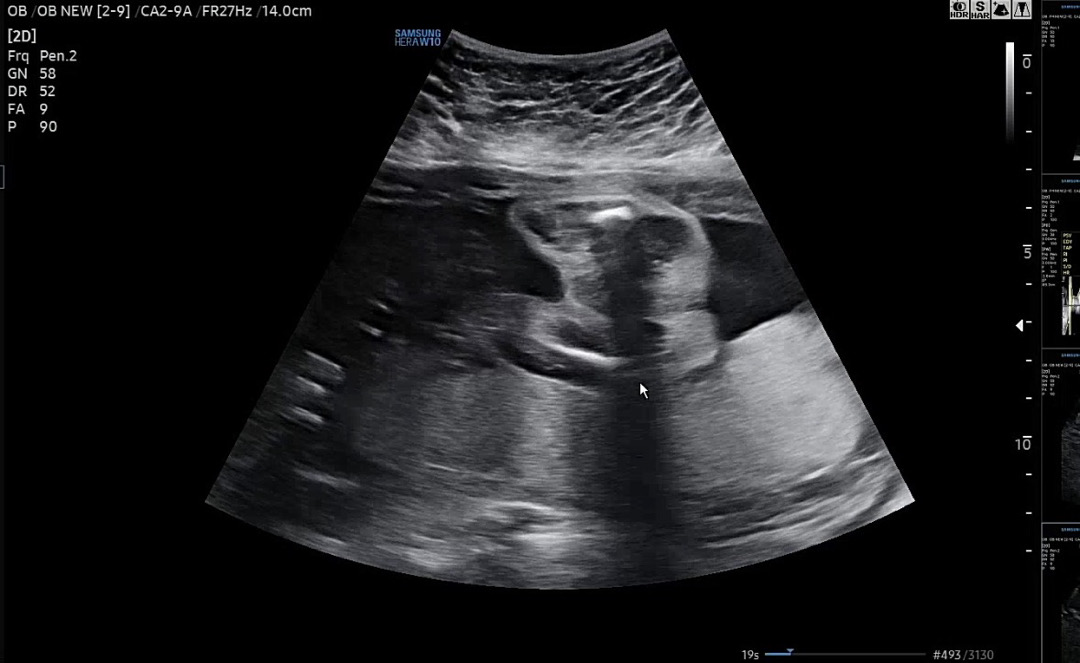

제눈엔 매끈한거 같은데 예비맘님들께서는 어때보이시나요??ㅠㅠ혹시 햄버거사인이 보이시나요??